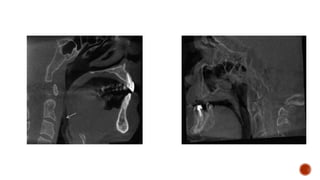

MIDSAGITTAL

ORTHOGONAL CBCT

IMAGE